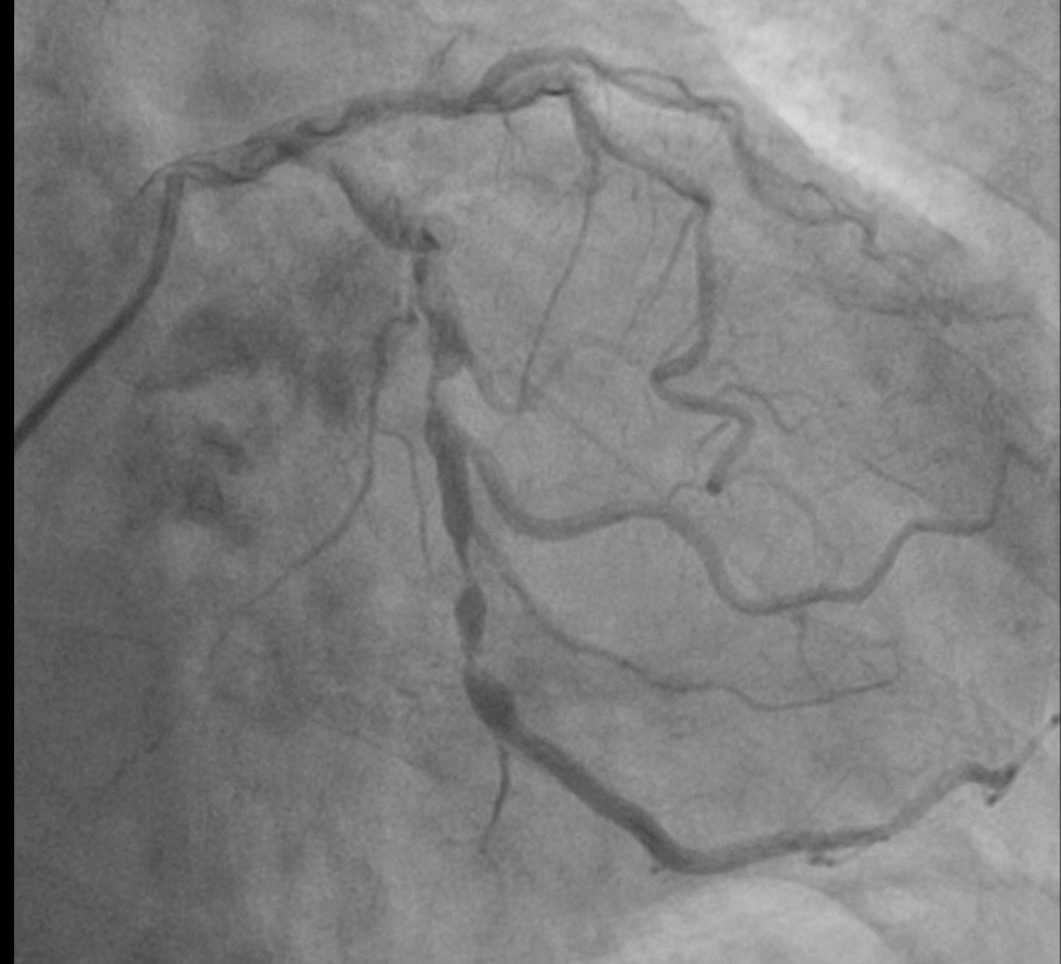

杨嗲嗲既往有“肺气肿”、“颈动脉粥样硬化”、 “胆囊结石”、 “前列腺增生”等病史。心脏彩超显示主动脉瓣钙化、重度狭窄并返流,冠脉影像显示冠状动脉病变也很严重。